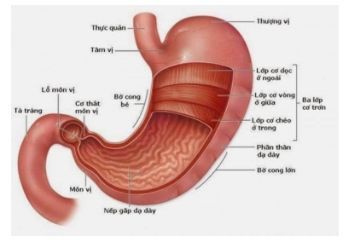

Dạ dày thực quản nằm ở đâu trong cơ thể?

Dạ dày là phần phình to nhất của ống tiêu hóa, phía trên nối với thực quản, phía dưới nối với tá tràng. Về cấu trúc, dạ dày có bốn phần chính: tâm vị, đáy vị, thân vị và môn vị. Tâm vị là điểm nối thực quản với dạ dày, thức ăn từ thực quản đi qua tâm vị để vào dạ dày không có van đóng kín mà chỉ có nếp niêm mạc, gọi là nếp van thực quản dạ dày. Đáy vị hình vòm, nằm ở phía dưới cơ hoành, bên trên và bên trái so với tâm vị. Bên dưới đáy vị là thân và là phần chính của dạ dày. Môn vị hình chiếc phễu giúp nổi dạ dày và tá tràng. Cơ thắt môn vị (một loại cơ trơn) nằm ở phía cuối của chỗ nối giữa dạ dày với tá tràng.

Nếp van thực quản – dạ dày nằm ở đâu?

Nếp van thực quản – dạ dày nằm ở chỗ nối giữa thực quản và dạ dày.